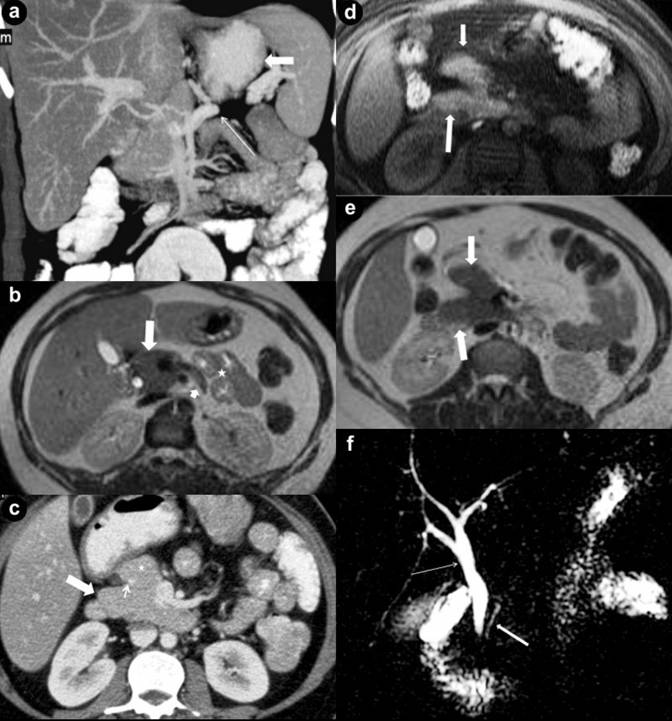

We measured the pancreatic duct length and diameter in all our patients. MR and MRCP images were used for obtaining the ductal measurements. We observed that in partial agenesis of the dorsal pancreas, the duct of Wirsung was shorter in length compared to the duct of Santorini. The duct of Wirsung was relatively longer in cases of complete agenesis of the dorsal pancreas (Table 1).

Table 1. Imaging findings on CT and MRI with MRCP. |

||||

|

Calcification |

Duct of Santorini’s length (mm) |

Duct of Wirsung’s length (mm) |

Type of agenesis |

Case #1 |

Absent |

14 |

Complete |

Case #2 |

Present |

11 |

5.4 |

Partial |

Case #3 |

21 |

From the above observation, we hypothesize that this variation may be due to the fact that when the pancreatic duct is single (as in complete agenesis, where only the duct of Wirsung is present) and it has to drain the head and uncinate process alone, its length has to be proportionately longer to drain the larger area. On the other hand when both ducts are present as in partial agenesis, the draining territory is shared between them; hence it (duct of Wirsung) develops to relatively shorter length.